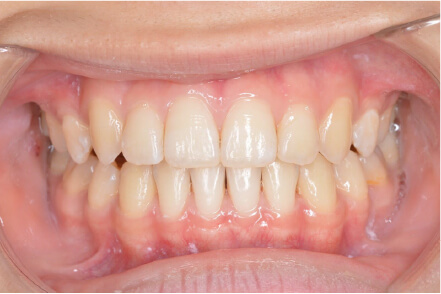

叢生の症例

10歳

/

女性

相談内容

スペース不足

カウンセリング・診断結果

myoからの移行。スペース不足のためインビザライン開始。

治療内容・方法

全額アライナー矯正

術後の経過・現在の様子

クリアライナー使用

治療のリスク

痛み・歯根吸収・歯肉退縮・虫歯・後戻り

費用・治療期間

(インビザのみ)385,000円、1年2ヶ月 + myo3年4ヶ月

トレーニングなど